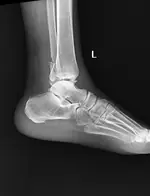

Cheville

Pied

Fractures malleolaires